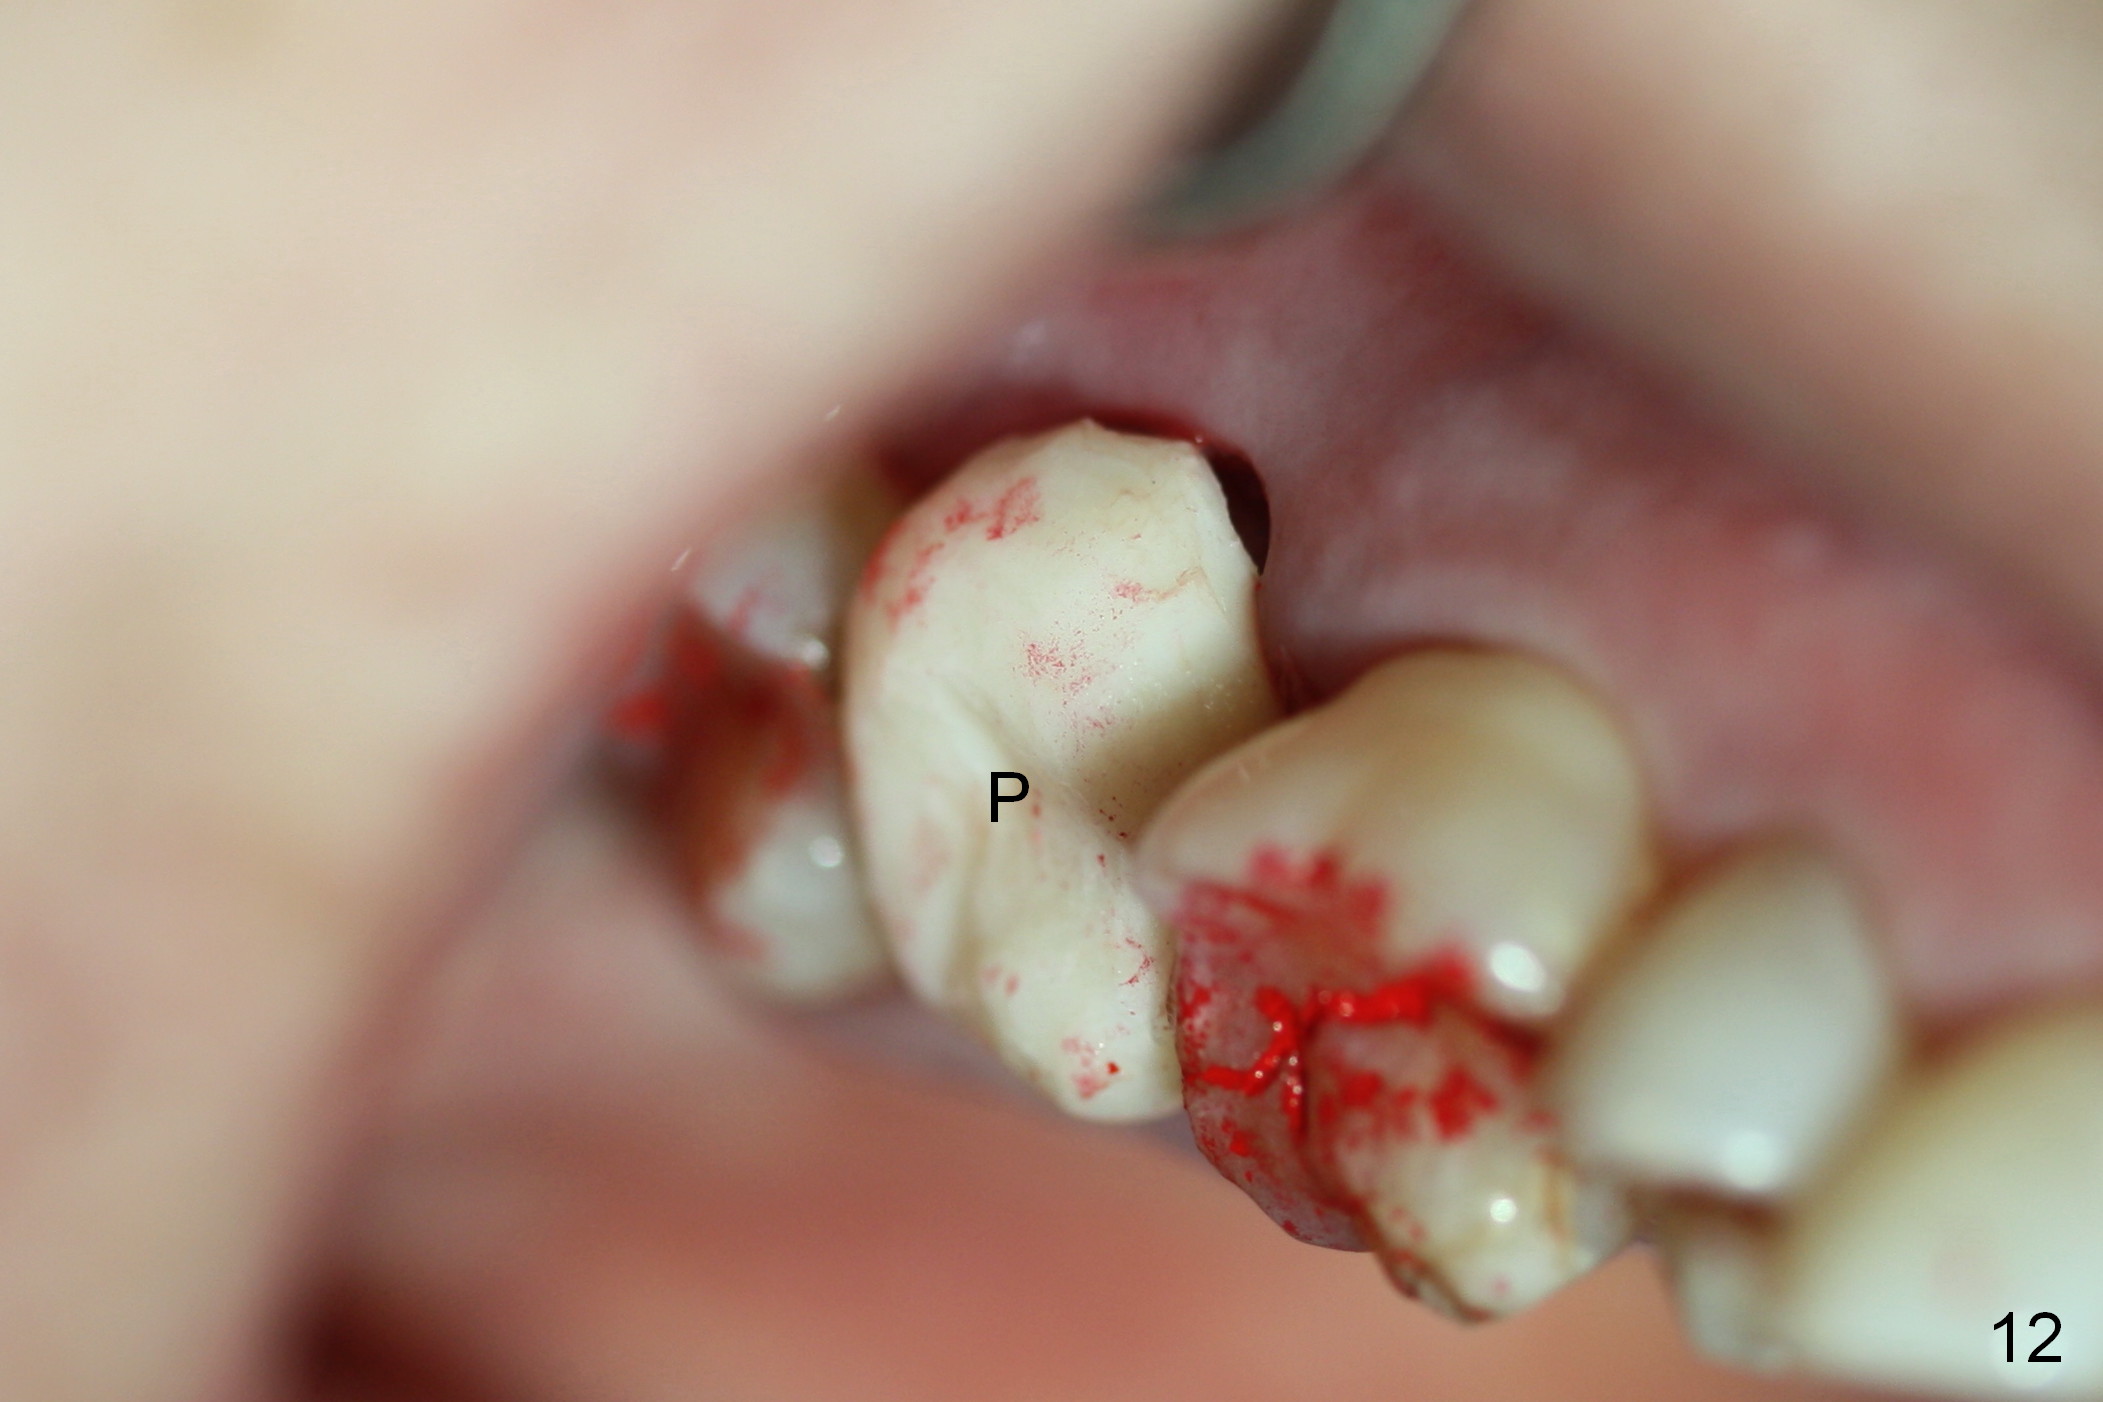

Probably due to bruxism, there is limited vertical restorative space. The margin is subgingival except buccal (Fig.10,11). An immediate provisional (Fig.12 P) appears to have to be fabricated to prevent soft tissue from covering the margin during osteointegration. It is our intention to make gingival envelop larger than the definitive crown cervix. It would be easier to remove a permanent cement later on for peri-implantitis prevention.